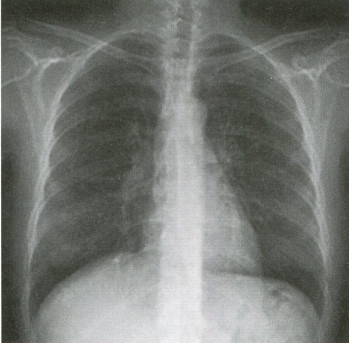

청진 및 기본진찰상 큰 이상소견은 없었으나 반복되는 기침 원인 확인 및 늑막염 및 폐렴 등의 가능성을 감별하기 위하여 흉부 엑스레이를 촬영하였으며 이상소견은 없으며 투약 후 경과를 보았습니다.